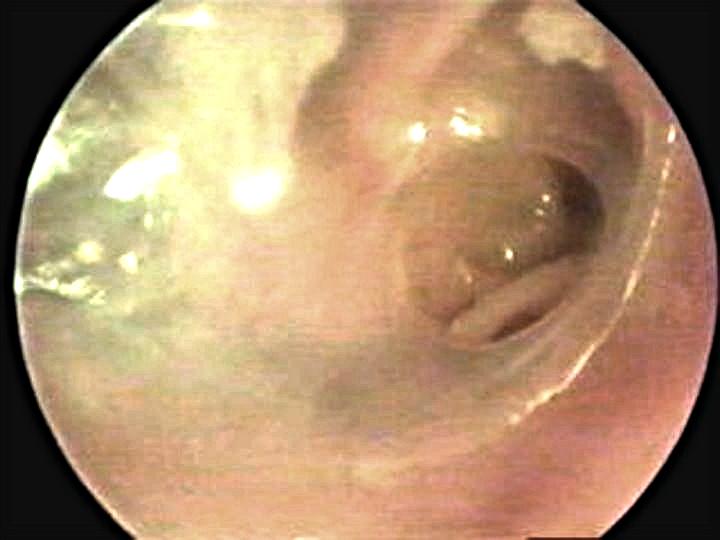

Gran

perforación timpánica

Se visualizan martillo estribo y yunque